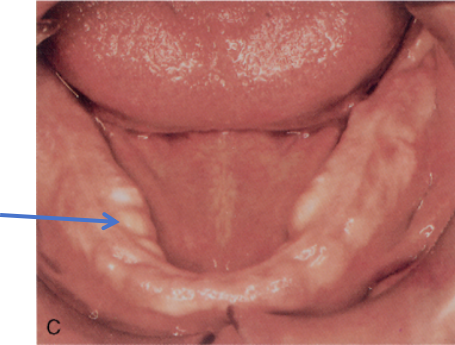

全口假牙需要适应一段时间。一开始有异物感、恶心、发音不清、口水增多、压痛、黏膜溃疡、咀嚼不便、易松动脱落等情况是正常的。全口假牙在使用过程当中出现黏膜压痛和溃疡是十分正常的,假牙在使用过程当中受到咀嚼力会下沉造成黏膜个别区域压力过大,便会出现压痕和溃疡,需要来医院进行数次调整,以达到黏膜均匀受力。但要切记,调改应少量多次,以免假牙被磨除过多,造成吸附力下降。在来调改义齿前一天,必须坚持佩戴假牙,这样医生能根据黏膜上的溃疡和压痕进行精准的调改。

图8 佩戴全口义齿后出现溃疡(箭头所指)